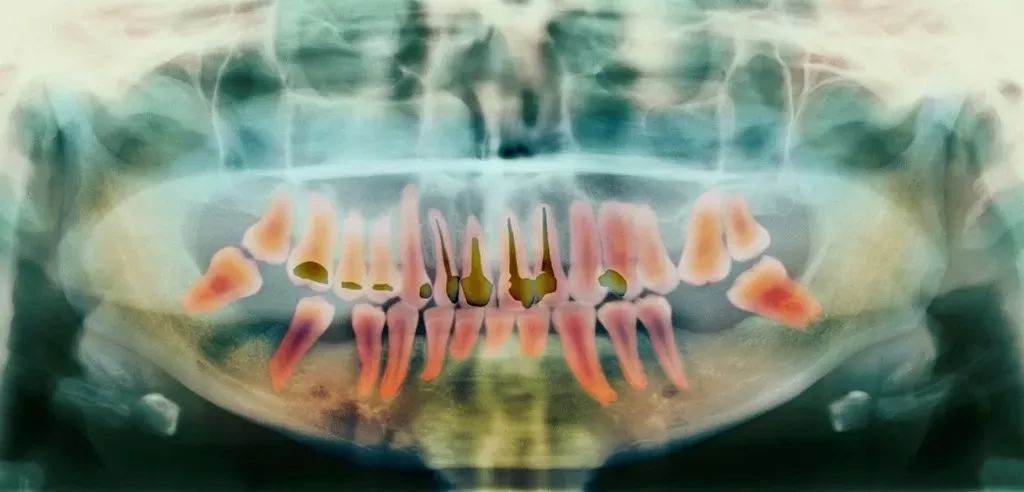

前牙根管需要治疗的牙根数量少,价格也就相对便宜;反之,后牙相较于前牙的价格会贵,双尖牙的根管治疗是最难的,因此,根管治疗的价格也是最贵的。

前面就讲过了,当蛀牙才刚刚萌发的时候进行治疗,只需要简单补牙就可以解决了;但当蛀牙侵害到牙髓和神经,就不得不根管治疗了。

所以,如果蛀牙刚刚开始就被发现,就可以及时治疗,简单修复便无大碍了。

但是蛀牙初期发生的时候往往不会有任何感觉,如果你已经感觉到酸楚或者疼痛了,可能已经晚了,这个时候就不得不进行根管治疗,耗时耗力又费钱了。